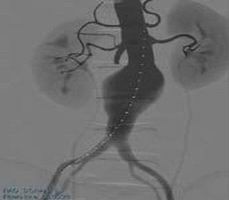

腹主動脈瘤修復(fù)手術(shù)模塊

可練習(xí)主動脈造影、主干精確開傘、對側(cè)腿使用腹膜支架、支架打開、球囊擴張等操作